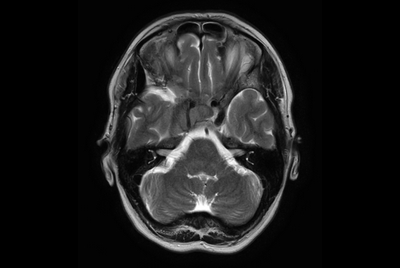

Brain overview